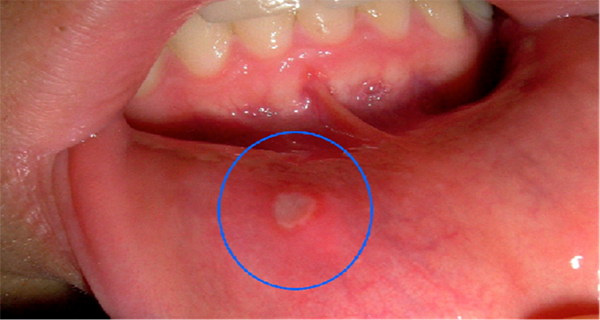

The medical name of the mouth ulcers is “Aphthous stomatitis”, which means “fiery wound”, describes the person who has them in his oral cavity. These small ulcers cause tremendous pain, and sometimes even impede swallowing of the food.

Ulcers are harmless viral infections that last several days to a week, but sometimes longer if untreated.